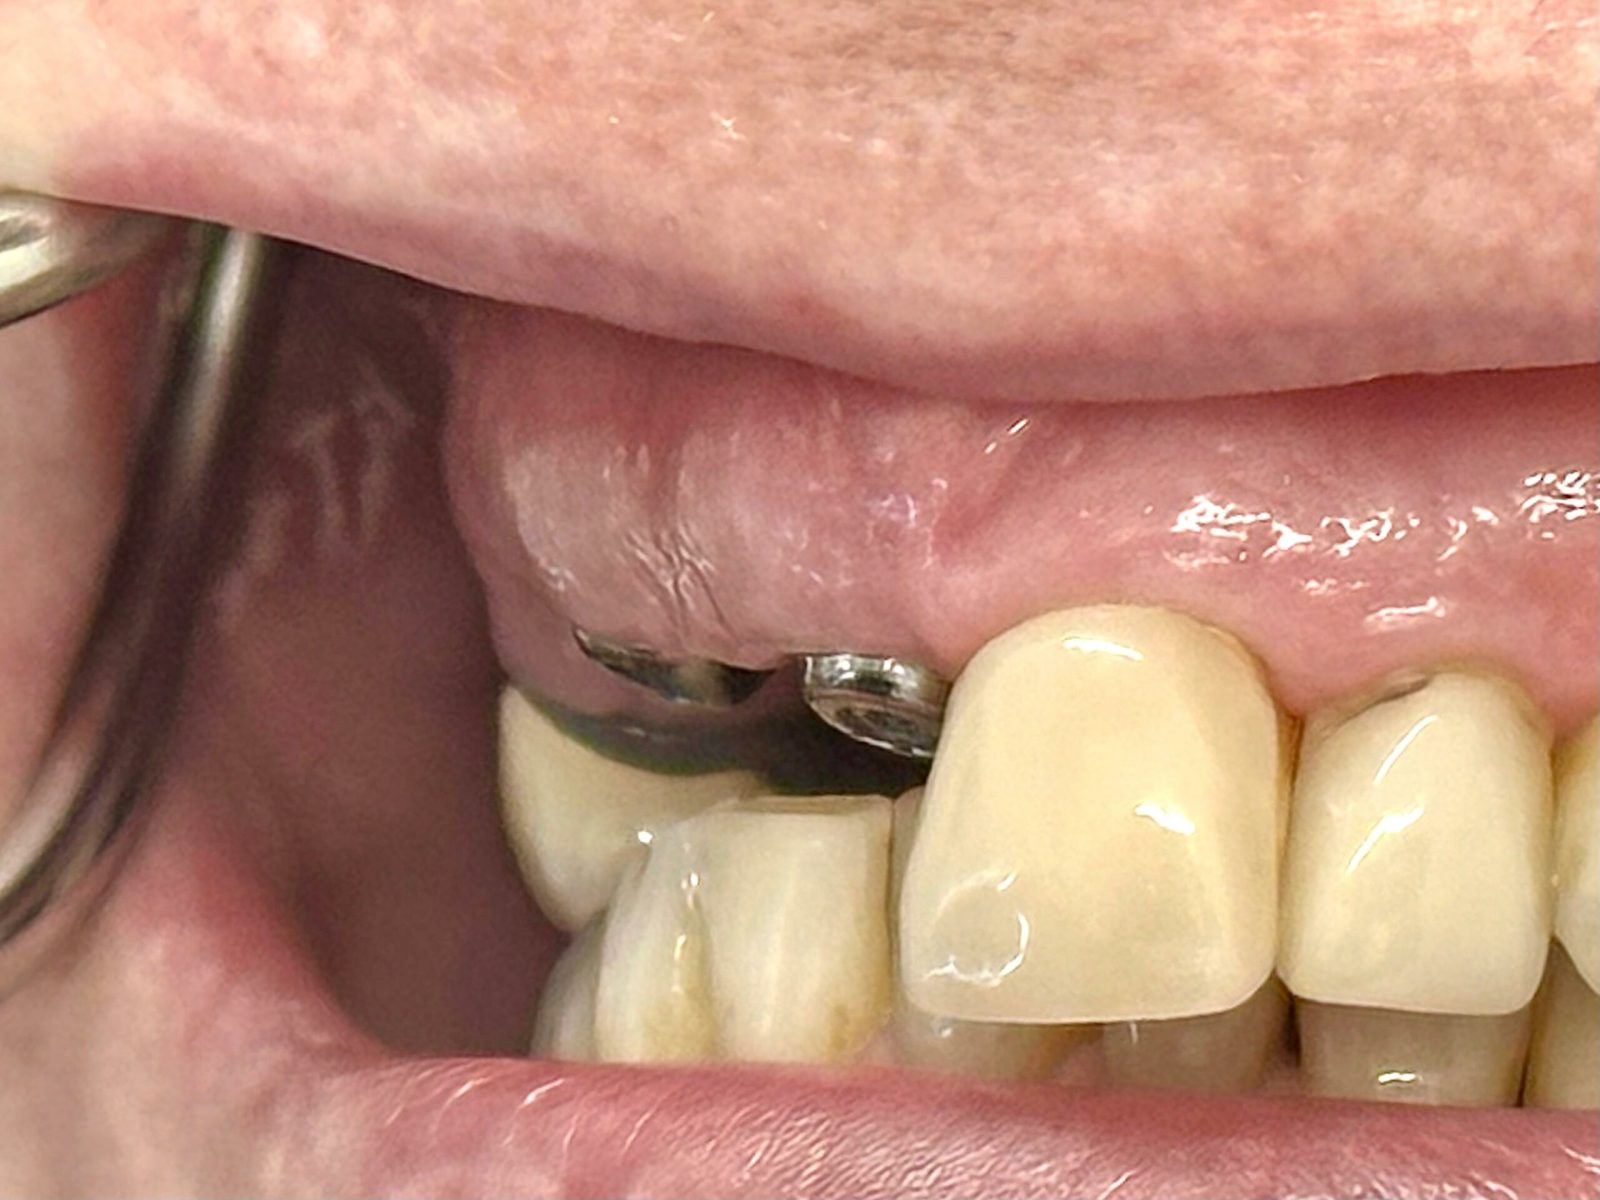

Single implant case in the anterior region, following digital planning to ensure precise positioning and optimal aesthetic outcome. Pre-operative CBCT analysis was used to assess bone volume and guide implant angulation, allowing for a prosthetically driven approach.

The implant was placed with careful attention to surrounding anatomical structures and soft tissue preservation. This allowed for stable integration and proper support of the final restoration. Healing was uneventful, with good tissue response and maintenance of gingival architecture.

The final crown was designed to match the adjacent teeth in shape, colour, and emergence profile, achieving a natural and harmonious result. Functional stability and aesthetic integration were both prioritised, delivering a predictable long-term outcome.